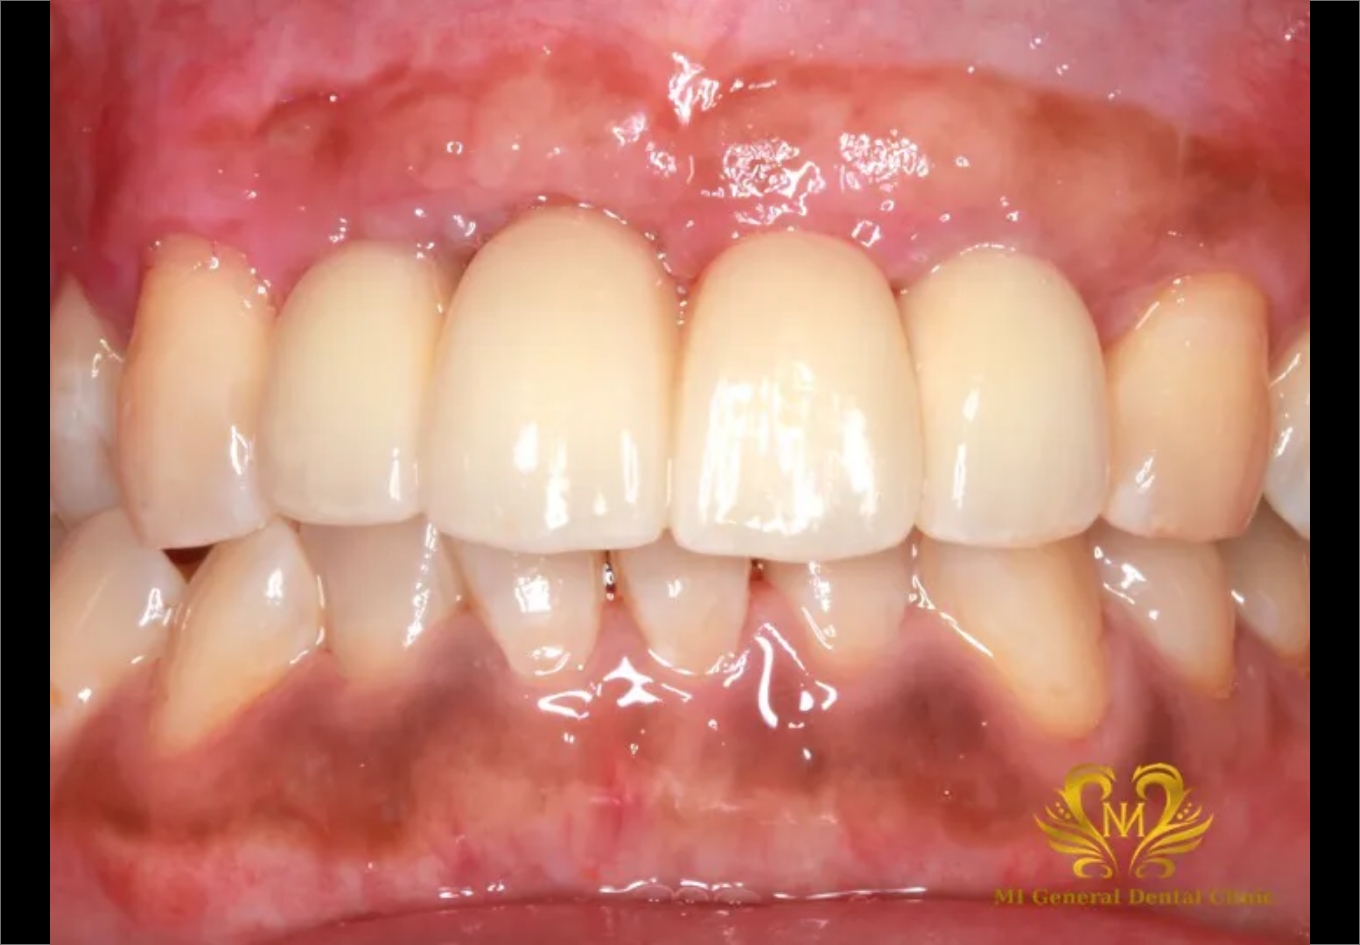

治療後

骨造成を行った後で、インプラント体の埋入。

インプラント体が骨と定着するのを待って仮歯で見た目や噛み合わせの調整をしてから型取りをして

綺麗なセラミックスの本歯を装着しました!!